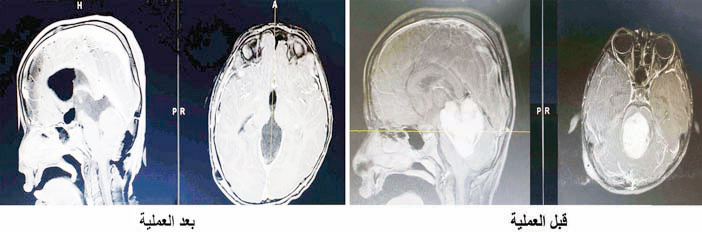

وأضاف د. مسعود أن الفريق الطبي المعالج والذي مُثل فيه كافة التخصصات ذات الصلة بالحالة المرضية، قرر التدخل جراحياً ووضع خطة علاجية متكاملة بدأت بزراعة جهاز داخل الدماغ لإزالة ضغط الاستسقاء الدماغي، ومن ثم خضع الطفل لعملية جراحية دقيقة ومعقدة، أجريت في وضعية الجلوس وتم فيها إزالة الورم بشكل كامل تحت المراقبة العصبية بأحدث الأجهزة، وبنهاية العملية التي استمرت قرابة الـ«8» ساعات، تم تحويل المريض إلى العناية المركزة للأطفال وهو بحالة مستقرة، ولاحقاً تم أخذ صورة رنين مغناطيسي للدماغ وأظهرت النتيجة نجاح العملية وأكدت إزالة الورم بالكامل دون إصابة المخ أو المخيخ أو أعصاب الدماغ بأي ضرر والحمد لله.